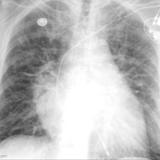

IPE 2

Date: 11/05/2005

Views: 3550